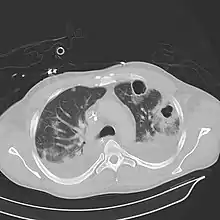

| Computed tomography (CT) scan of chest showing bilateral pneumonia with abscesses, effusions, and caverns. 37-year-old male. | |

A subpleural abscess.